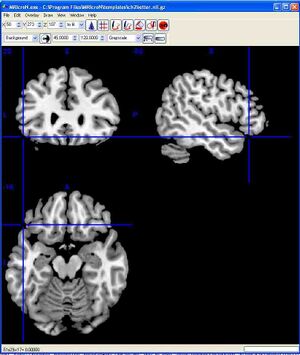

After successfully starting the program, you should see the following window. To make the images easier to see, you can enlarge the window. Go to Step 2, below. For Macintosh: The following instructions were tested with Mac OSX 10.8.2 running Safari. For different versions of OSX or other web browsers, the steps may be slightly different.

You should see the following window. To make the images easier to see, you can enlarge the window. To see only one plane enlarged, click View/Axial Only. For Linux (or if the above instructions don't work): please go to http://www.mccauslandcenter.sc.edu/mricro/mricron/install.html You are on your own for installation! REQUIRED Step 2: Explore the brain and learn structures found in labs 8 and 9Regardless of the platform (PC or Mac), the top left of the window shows a coronal view of the brain. The top right of the window shows a sagittal view of the brain. The bottom left of the window shows an axial (horizontal) view of the brain. Click the mouse at any brain location to move the blue viewing crosshairs. The dataset name is listed at the top of the MRIcroN window in Windows, at the bottom of the window for Mac. The correct brain to view is the "ch2" file (ch2.nii.gz). Load this file by selecting "File/Open/Templates/ch2.nii.gz". At the top of the program window are three boxes labelled "x", "y" and "z" that show the brain location. Enter each of the co-ordinates (x,y,z) listed below into MRIcron. This will take you to the structure whose name is on the first column. This material will make up part of the testing materials for these laboratories (lab exams). Name of structure / Coordinates of structure (enter into x,y,z boxes in MriCron)